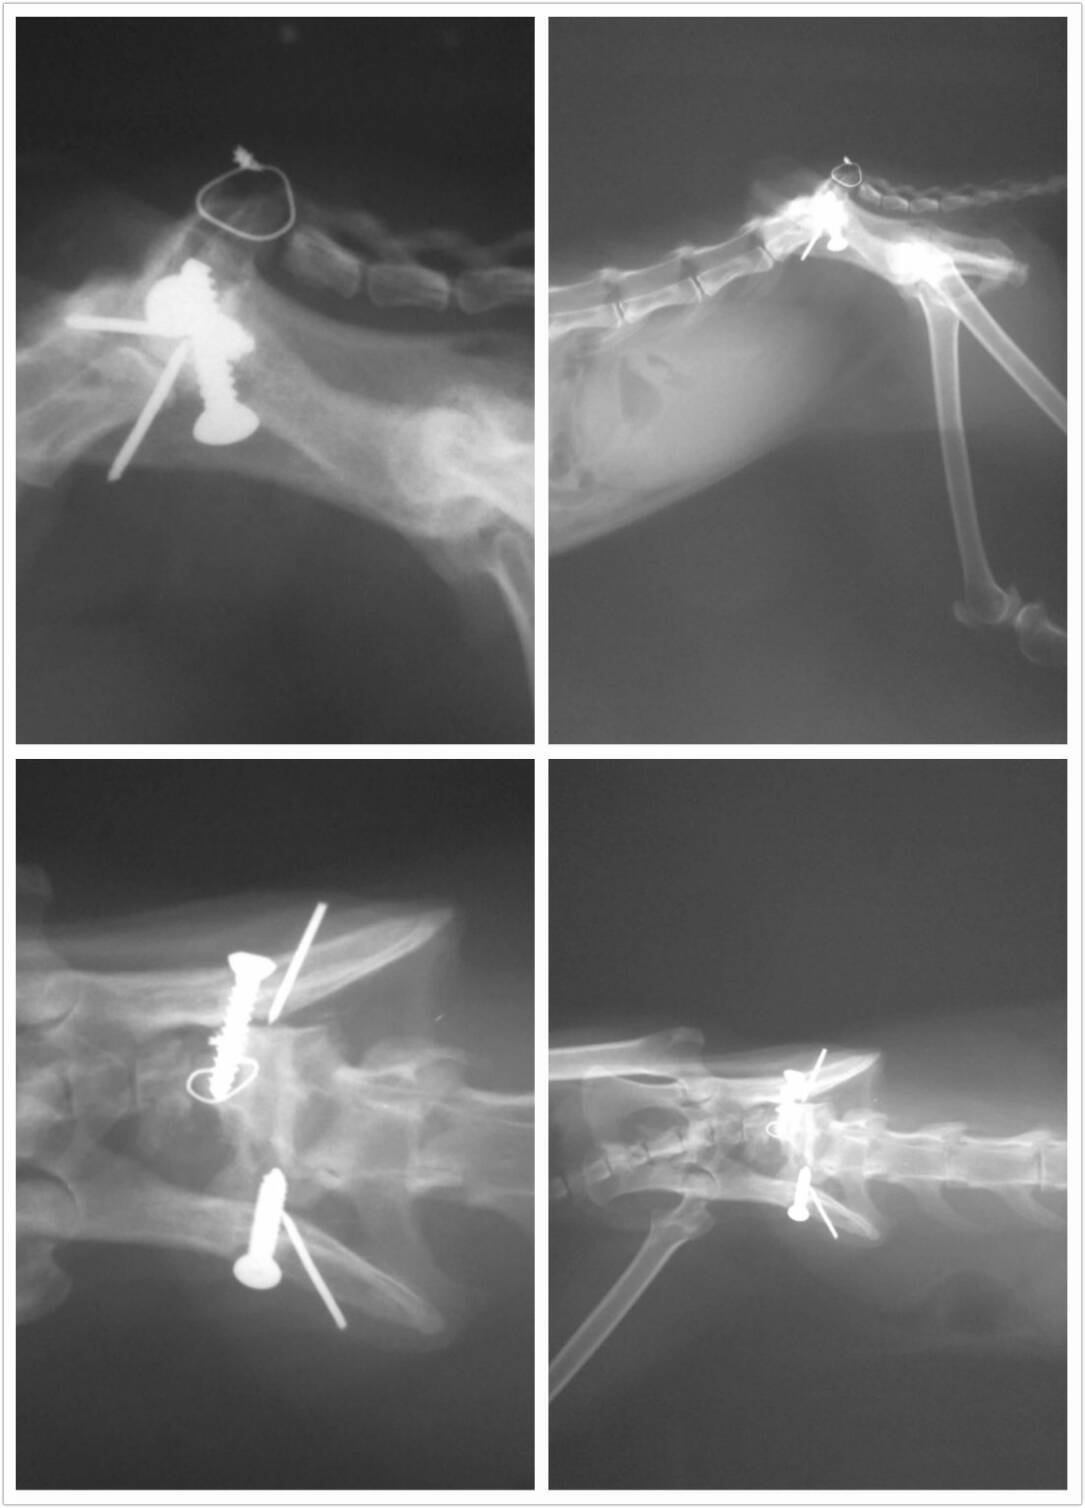

醫生診斷此貓咪(0227-1M)為公貓已結紮,有鼻氣管炎,臉部有傷口且因傷口收縮造成上眼臉外翻,X光檢查發現之前此貓腸薦關節有做過手術,但骨釘及螺釘已走位,導至骨盆已錯位,且尾巴骨頭也有斷及有外傷,用力夾尾巴發現尾巴已無痛覺,代表其神經已斷,尾外傷的部份有可能是脫行造成, 驗血結果為白血求球及腎指數過高,有貓愛滋,一開始初步已先點滴及輸液給藥治療,並裝上食道胃管管。貓咪到院後眼睛上方額頭也莫名的掉了一塊皮,感覺這貓很辛苦,整個不對勁,不太像隻貓>< 讓人非常心疼

等貓咪狀況穩定,3/10醫生才幫貓咪做截尾手術和拔除骨釘的動作,之後右眼3/25先做手術,恢復過程醫生觀察貓咪的狀況,隔些日子才又做左眼手術。經過醫院辛苦地照顧和醫療總算出院了。 目前安置著,希望貓咪不再受苦,感謝大家來幫忙他,讓他接受好的醫療,有了全新的幸福生活^^